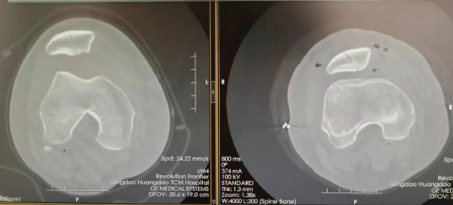

14岁学龄期女孩因右膝外伤后剧痛、活动受限入院,影像学显示髌骨下缘骨水肿信号明显,伴软骨剥脱,髌骨向外脱位,查体发现右膝肿胀,髌骨压痛明显,恐惧试验阳性,诊断为髌骨骨折、髌骨脱位。

11岁女孩因外伤致髌骨骨折、髌骨脱位,影像学检查发现髌骨下缘骨水肿信号明显,骨折端向髌骨后侧撕脱,伴软骨剥脱,髌骨向外脱位。

患者髌骨骨折伴髌骨向外脱位,按照传统手术方式,创伤较大,膝前方将遗留约6-8cm手术瘢痕且术后恢复较慢。胡建强科主任经过仔细分析,认为患者年龄较小,优先适用微创手术方案,经过术前精细手术规划,骨伤一科团队运用关节镜手术,实现骨折复位及髌骨脱位治疗。患者术后多次随访,目前膝关节已无明显疼痛不适,活动度趋于正常。